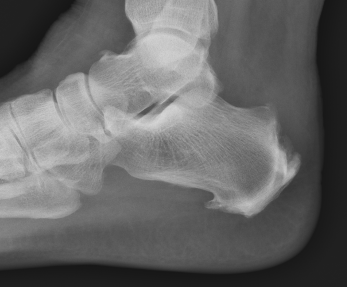

X-ray

Insertional achilles tendon spurs

- also present in asymptomatic patients

Calcification of bone-tendon interface with spur

Haglund's Deformity

- bony protuberance of posterosuperior calcaneus

Pavlov's parallel pitch lines

- lateral weight bearing x-ray

- draw parallel pitch lines

- defines Haglund's deformity to be removed (above second line)

Fowler's angle - Normal < 70° / Abnormal > 80°